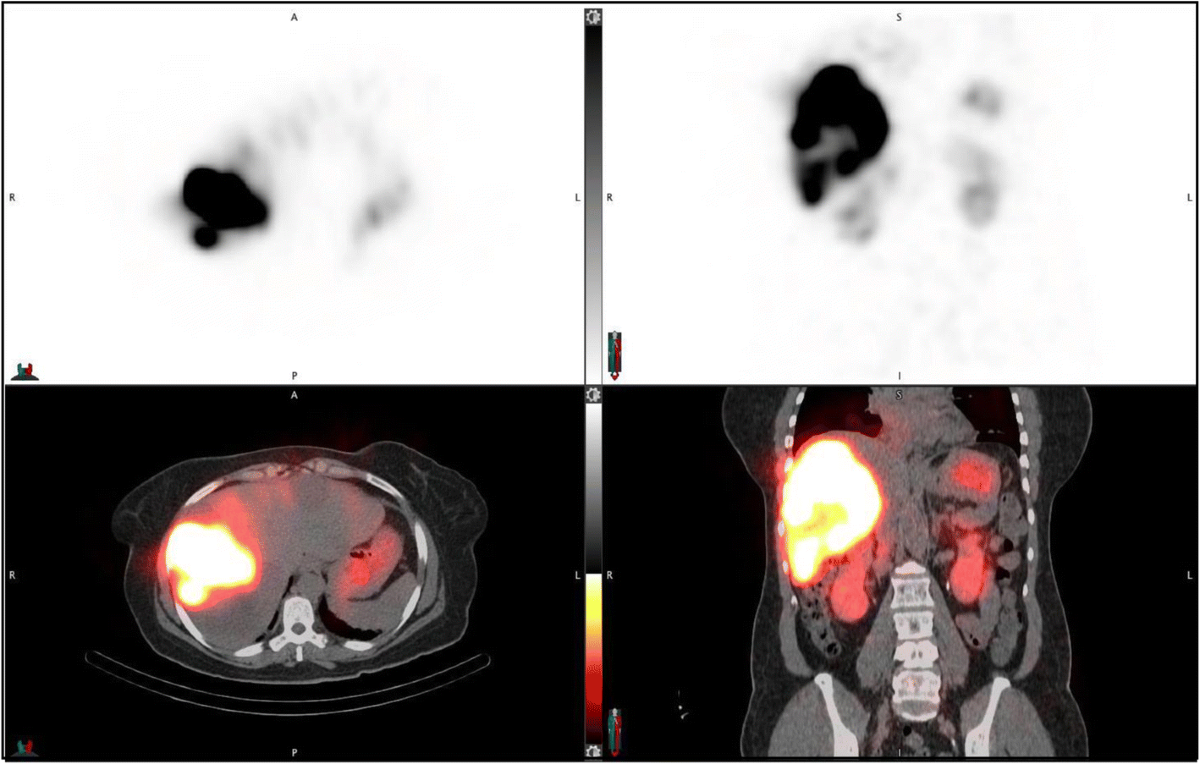

79 M with PMH of CKD, HLD, prostate cancer s/p prostatectomy + radiation presenting with feelings of fogginess, upset stomach, and diarrhea. Originally worked up at OSH, imaging concerning for a hepatic mass.

148/77 mmHg / 95 bpm / 15 breaths/min / 98.1°F / 98 ORA

sclera anicteric, no jaundice

AST 112, ALT 34, Alk Phos 202, CEA 2, CA 19-9 4